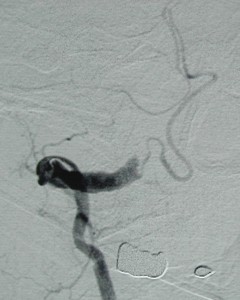

<左椎骨動脈撮影:右椎骨動脈と動脈瘤は写らなくなった(治癒)>

この患者さんは、15年経った今でも私の外来に来て、高血圧の治療をきちんと受けておられます。もちろん、後遺症なく元気にされておられます。

本当によかったです。